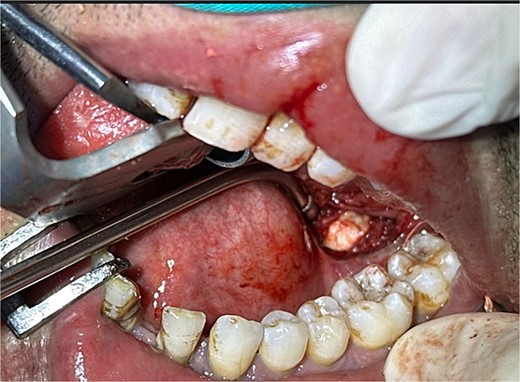

The accuracy of navigation was periodically verified by referencing stable bony landmarks, such as the mental foramen and mandibular condyles, with the navigation probe. Realignment was conducted as needed to ensure consistent anatomical mapping and precise localization of the submandibular stone (Fig. 2). After surface registration, a 1 cm mucosal incision was made intraorally at the nearest point indicated by the navigation pointer, parallel to the anticipated course of the Wharton duct. Blunt dissection was performed to expose the duct, with navigation toward the stone guided by the system. Great care was taken to protect the lingual nerve throughout the procedure. The depth of dissection was gradually advanced by periodically verifying the position with the navigation pointer probe (Fiagon) to maintain precision. During dissection, the stone was accurately located within the gland parenchyma using real-time visualization, and it became palpable, distinguished by its unique color and texture (Fig. 3). The stone was fragmented and removed in pieces because it was fixed (Fig. 4). The surgical field was flushed with saline to remove any residual stone debris, and the incision was closed with 4/0 Vicryl, which is an absorbable suture.

Fragments of the submandibular gland stone extracted during surgery.